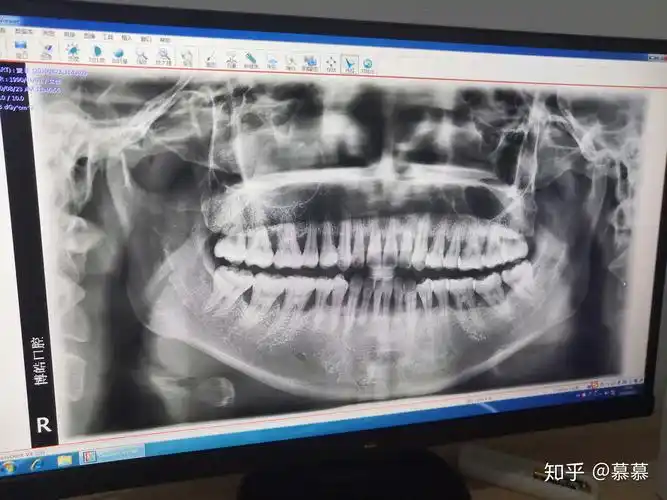

检查:结合cbct,36牙槽骨吸收严重,无保留价值.

这个牙槽骨吸收的严重吗?

牙槽骨吸收是不是很严重